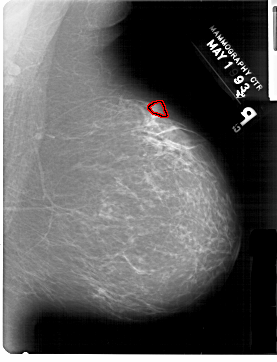

A_1421_1.RIGHT_CC

RIGHT_CC LINES 6871 PIXELS_PER_LINE 4621 BITS_PER_PIXEL 12 RESOLUTION 43.5 OVERLAY

FILE: A_1421_1.RIGHT_CC.OVERLAY

TOTAL_ABNORMALITIES 1

ABNORMALITY 1

LESION_TYPE MASS SHAPE IRREGULAR MARGINS ILL_DEFINED

ASSESSMENT 4

SUBTLETY 2

PATHOLOGY BENIGN

TOTAL_OUTLINES 1

BOUNDARY